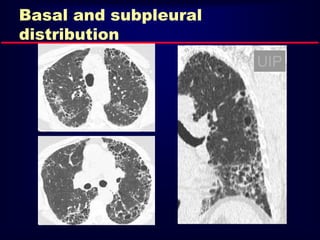

Basal and subpleural

distribution

UIP

Usual Interstitial Pneumonia UIP HRCTFindings Reticular opacities, thickened intra- and interlobular septa Irregular interfaces Honey combing and parenchymal distorsion Ground glass opacities (never prominent) Basal and subpleural predominance